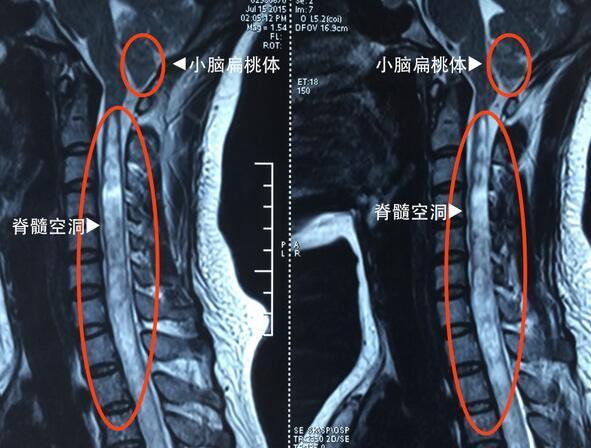

脊髓空洞是脊髓的一種慢性、進(jìn)行性病變,病因不明,其病變特點(diǎn)是脊髓(主要是灰質(zhì))內(nèi)形成管狀空腔以及膠質(zhì)(非神經(jīng)細(xì)胞)增生。脊髓空洞常發(fā)于頸部脊髓,病變累及延髓時(shí),則稱為延髓空洞癥。那么脊髓空洞癥有哪些癥狀呢?

脊髓空洞癥的發(fā)病年齡通常在20-30歲,女性較男性多見(jiàn),病程進(jìn)展較為緩慢,最早出現(xiàn)的表現(xiàn)是階段性分布的感覺(jué)障礙。